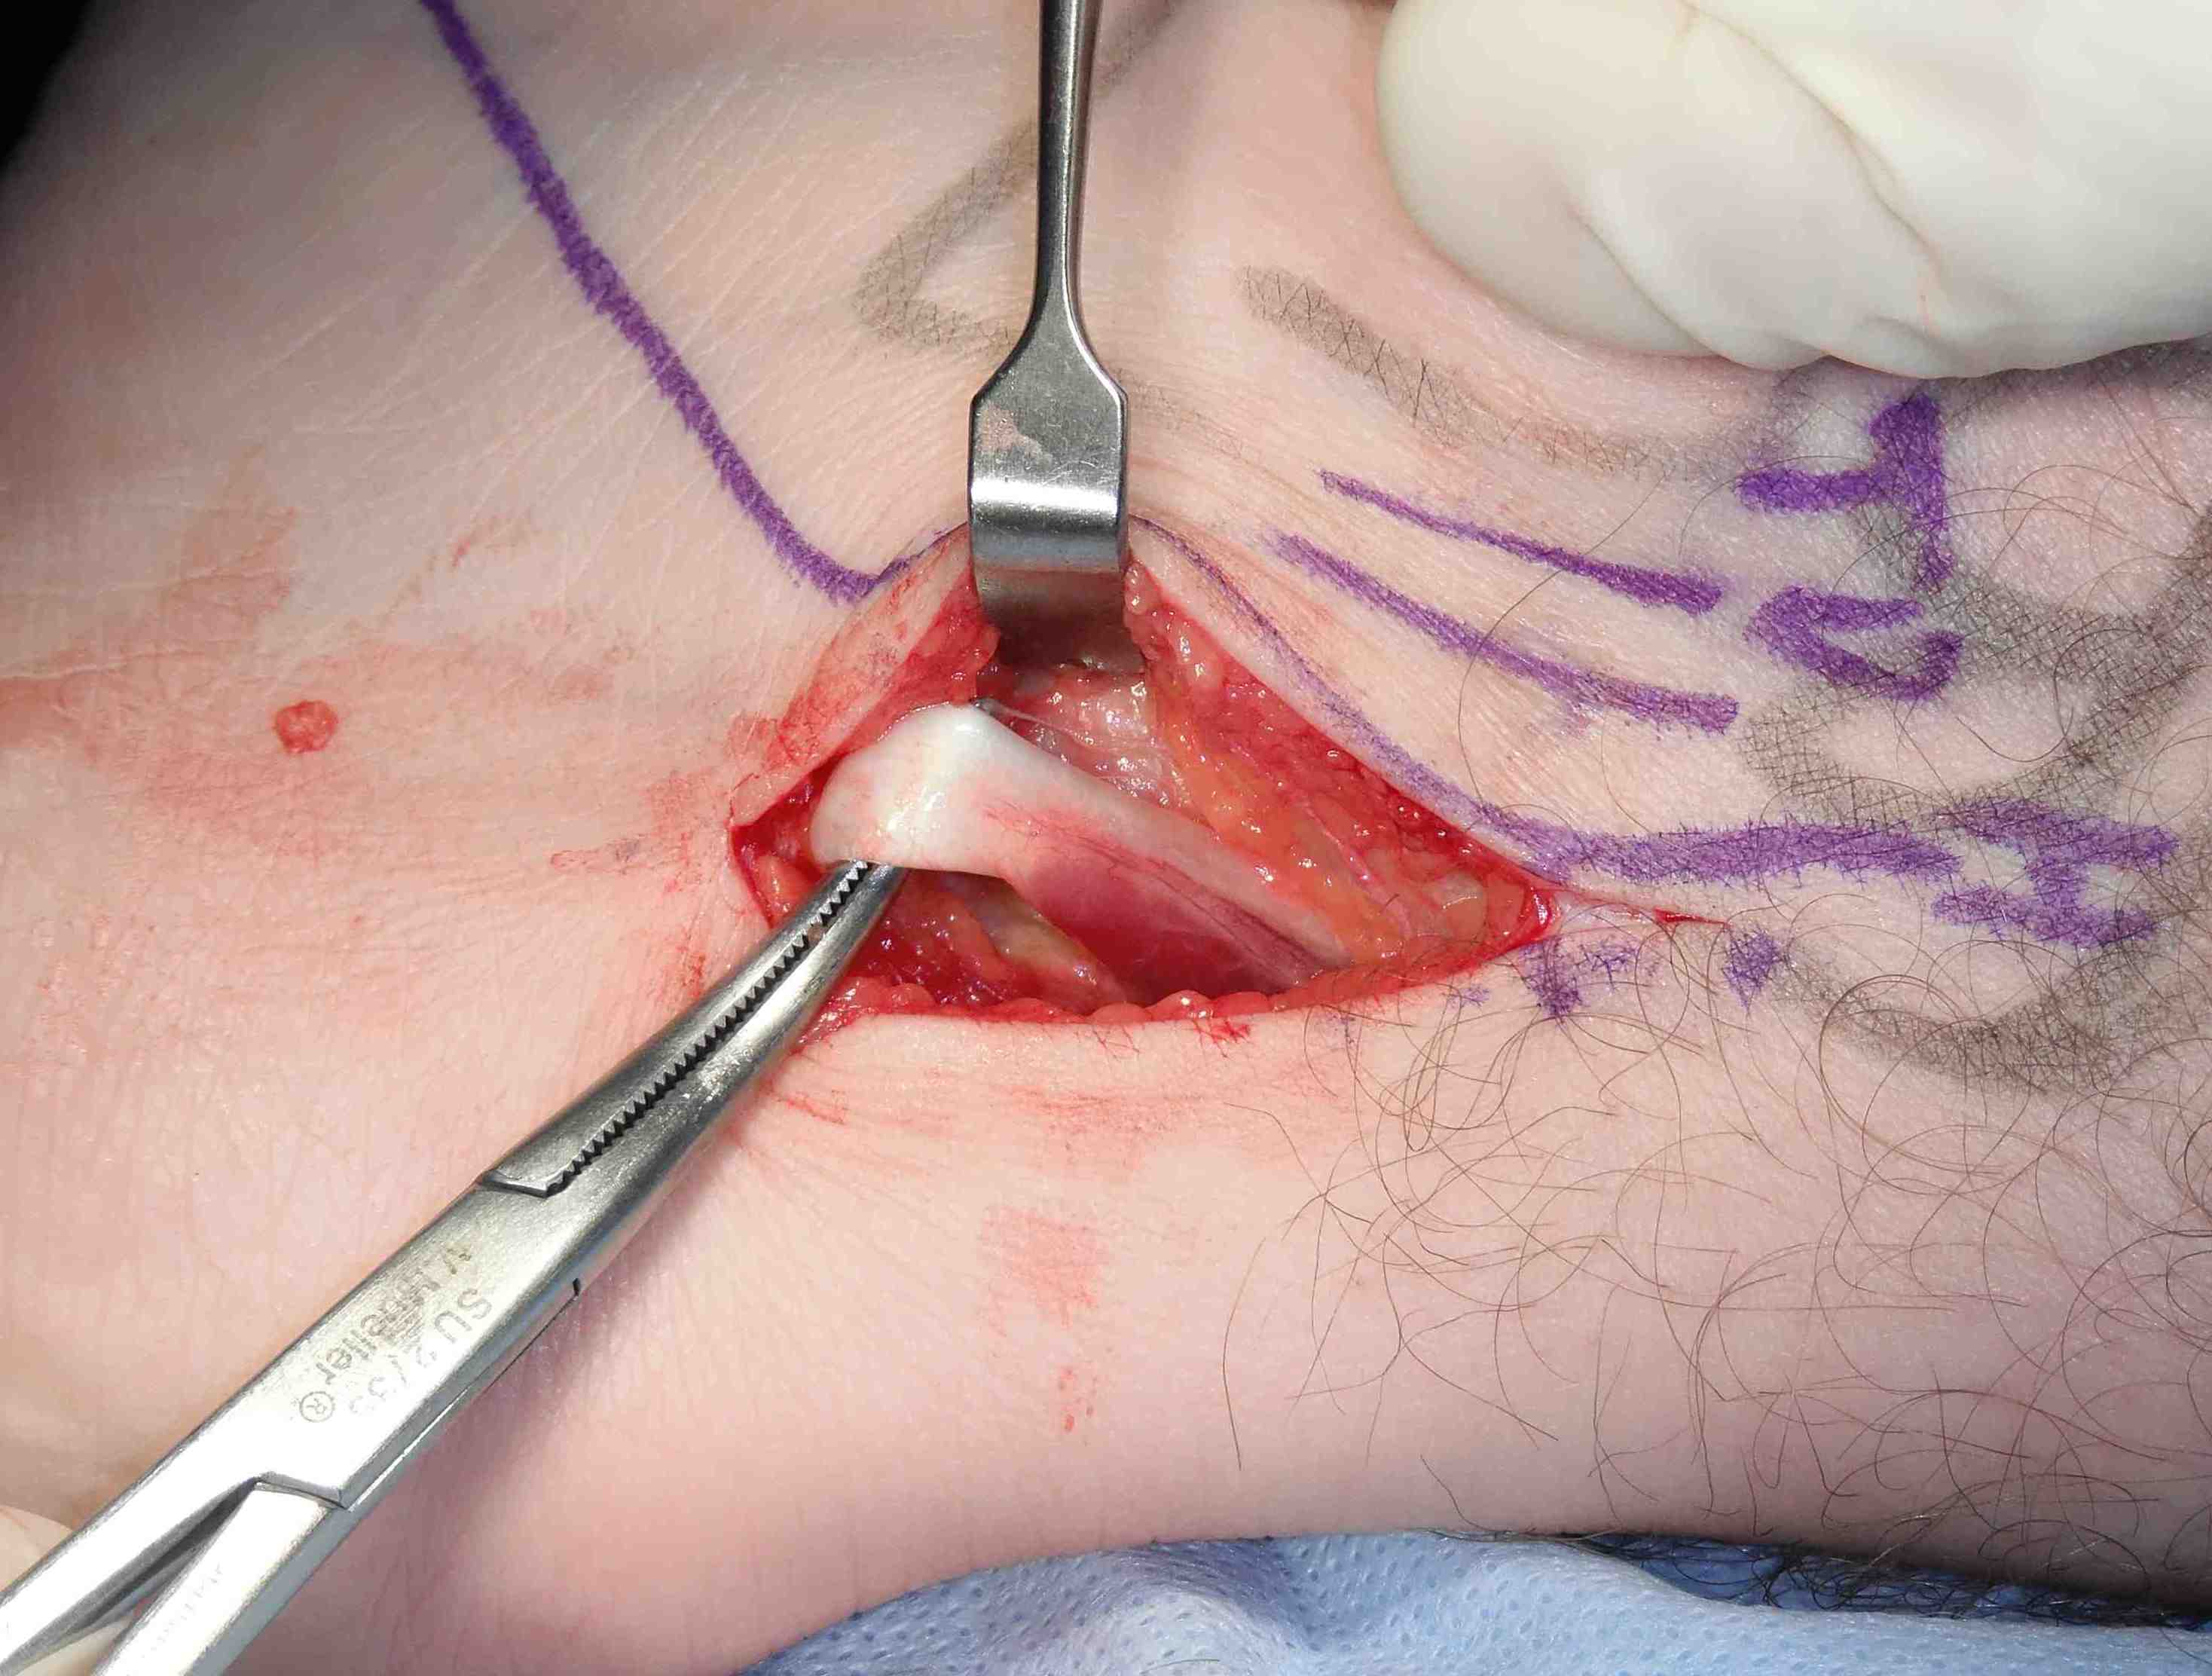

Open FHL release and os trigonum excision

Posteromedial approach

- incision between medial malleolus and T achilles

- divide superficial retinaculum

- neurovascular bundle immediately anterior

Identify FHL by moving great toe

- open FHL fibro-osseous tunnel releasing FHL compartment

- retract FHL anteriorly

Open posterior capsule over os trigonum and excise

Posteromedial approach and identification of FHL fibro-osseous tunnel

FHL identified and released, retracted anteriorly, capsule incised and os trigonum exposed